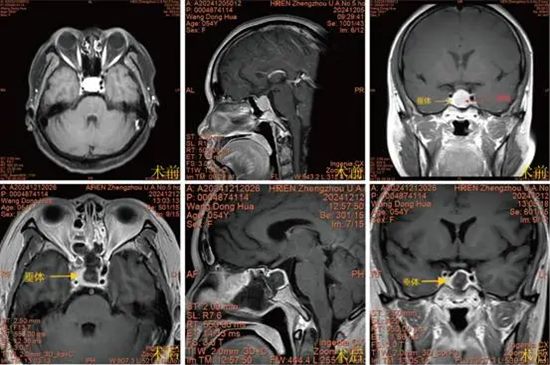

王某某,女,54岁,“间断头痛1年余”,查体:无视力减退及视野缺损。MRI:鞍区占位,考虑垂体大腺瘤(1.7cm*1.5cm*1.8cm)。术前PRL:24.81ng/mL。术后第一天:PRL:3.9ng/mL。达到治愈标准。

注:正常垂体受肿瘤压迫,紧贴右侧海绵窦内侧壁,神经内镜下假包膜外完整切除肿瘤,术后复查肿瘤全切,无残留。